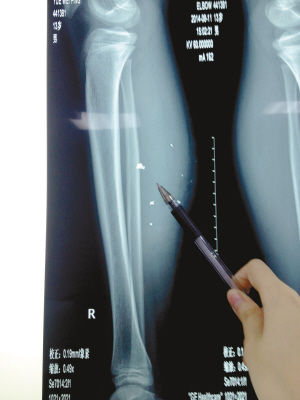

X光片顯示:手機(jī)電池內(nèi)的物質(zhì)被炸進(jìn)了小平的右小腿里

8月10日凌晨,小平轉(zhuǎn)院至重慶醫(yī)科大學(xué)附屬兒童醫(yī)院。小平的主治醫(yī)生骨科二病房周悅航醫(yī)生介紹,入院時(shí)小平右小腿腫脹,經(jīng)檢查,發(fā)現(xiàn)有爆炸傷伴異物殘留。傷口較深,約1.5厘米~2厘米,手機(jī)爆炸后進(jìn)入患兒小腿的異物約有10處。周悅航說,由于進(jìn)入皮膚的異物較多,已深入肌肉,且比較分散,最深的一塊貼近骨頭,可能需要多次手術(shù)。

另外,醫(yī)生擔(dān)心手機(jī)爆炸后金屬物進(jìn)入患兒體內(nèi)可能會(huì)對(duì)患兒肌肉造成損傷,所以需盡快手術(shù)。據(jù)悉,8月14日上午,小平將接受小腿爆炸傷清創(chuàng)與異物取出術(shù)。